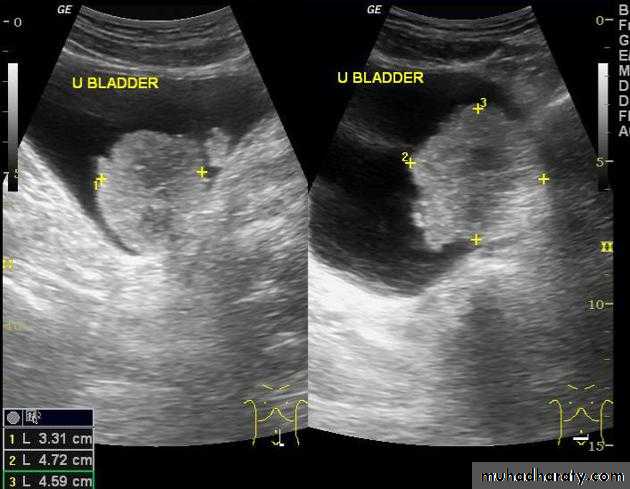

BPH with elevated bladder base